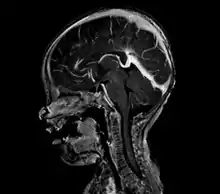

An AVM diagnosis is established by neuroimaging studies after a complete neurological and physical examination.[4][9] Three main techniques are used to visualize the brain and search for AVM: computed tomography (CT), magnetic resonance imaging (MRI), and cerebral angiography.[9] A CT scan of the head is usually performed first when the subject is symptomatic. It can suggest the approximate site of the bleed.[2] MRI is more sensitive than CT in the diagnosis of AVMs and provides better information about the exact location of the malformation.[9] More detailed pictures of the tangle of blood vessels that compose an AVM can be obtained by using radioactive agents injected into the blood stream. If a CT is used in conjunctiangiogram, this is called a computerized tomography angiogram; while, if MRI is used it is called magnetic resonance angiogram.[2][9] The best images of an AVM are obtained through cerebral angiography. This procedure involves using a catheter, threaded through an artery up to the head, to deliver a contrast agent into the AVM. As the contrast agent flows through the AVM structure, a sequence of X-ray images are obtained.[9]